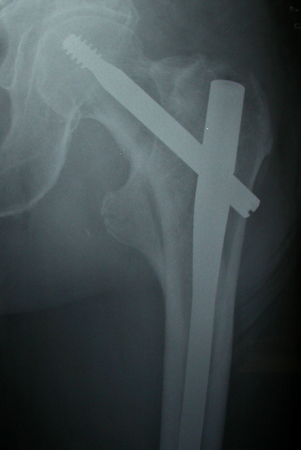

Com os padrões de fratura extracapsulares, a estabilidade das fraturas com desvio geralmente depende da extensão da cominuição e, mais especificamente, a cominuição do córtex medial. Os padrões das fraturas intertrocantéricas simples em 2 segmentos sem cominuição do côndilo medial (córtex) geralmente são considerados estáveis. Fraturas intertrocantéricas em 3 ou 4 segmentos com ruptura do córtex posteromedial ou fratura de obliquidade reversa são consideradas instáveis.[3][51][Figure caption and citation for the preceding image starts]: Radiografia anteroposterior inicial mostrando uma fratura intracapsular do quadril esquerdo com desvioDo acervo de Bradley A. Petrisor, MSc, MD, FRCSC e Mohit Bhandari, MD, MSc, FRCSC [Citation ends].com.bmj.content.model.Caption@52066261[Figure caption and citation for the preceding image starts]: Fratura intertrocantérica instável na radiografiaDo acervo de Bradley A. Petrisor, MSc, MD, FRCSC e Mohit Bhandari, MD, MSc, FRCSC [Citation ends].com.bmj.content.model.Caption@40745e54